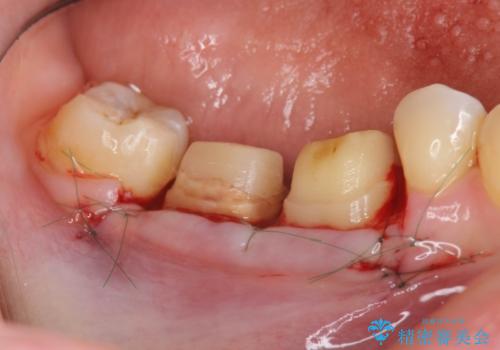

歯周ポケットの除去を併用したセラミック治療

適合や審美性に優れるセラミック治療を行う前に、歯周病の問題を歯周外科を行うことで解決し将来的に不安のないような口腔内環境を整備していきます。

治療前に4-5mm程度あった歯周ポケットは全て2mm以内となり、非常に清掃性が高く、歯周病の再発しずらい環境に整えた上でのセラミック治療を実践することができました。

- 外科手術のため、術後に痛みや腫れ、違和感を伴います

- 歯周組織再生治療は患者様の状態によって術後の経過が異なります(見た目が改善しない場合もあります)